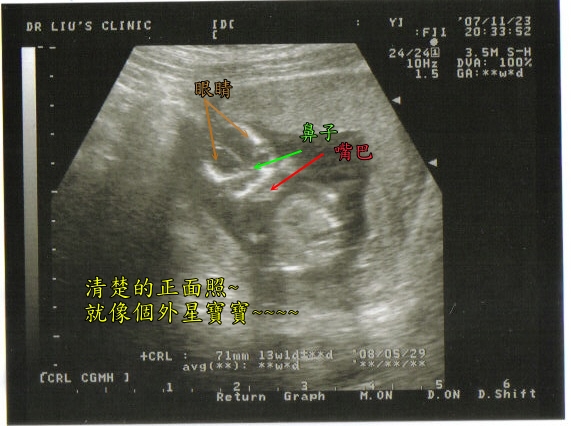

小米跟上次比較起來~

這次最不一樣的就是他的五官可以明顯的看出來了~

大家看的出來嗎~~~整個就像個外星寶寶一樣~~

現在還沒辦法想像跟猜測小米以後會長的像我還是會像他老爸~哈~會不會想太多了一點~`

小米跟上次比較起來~

這次最不一樣的就是他的五官可以明顯的看出來了~

大家看的出來嗎~~~整個就像個外星寶寶一樣~~

現在還沒辦法想像跟猜測小米以後會長的像我還是會像他老爸~哈~會不會想太多了一點~`